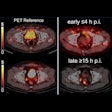

Emerging PET tracer for prostate cancer displays promise